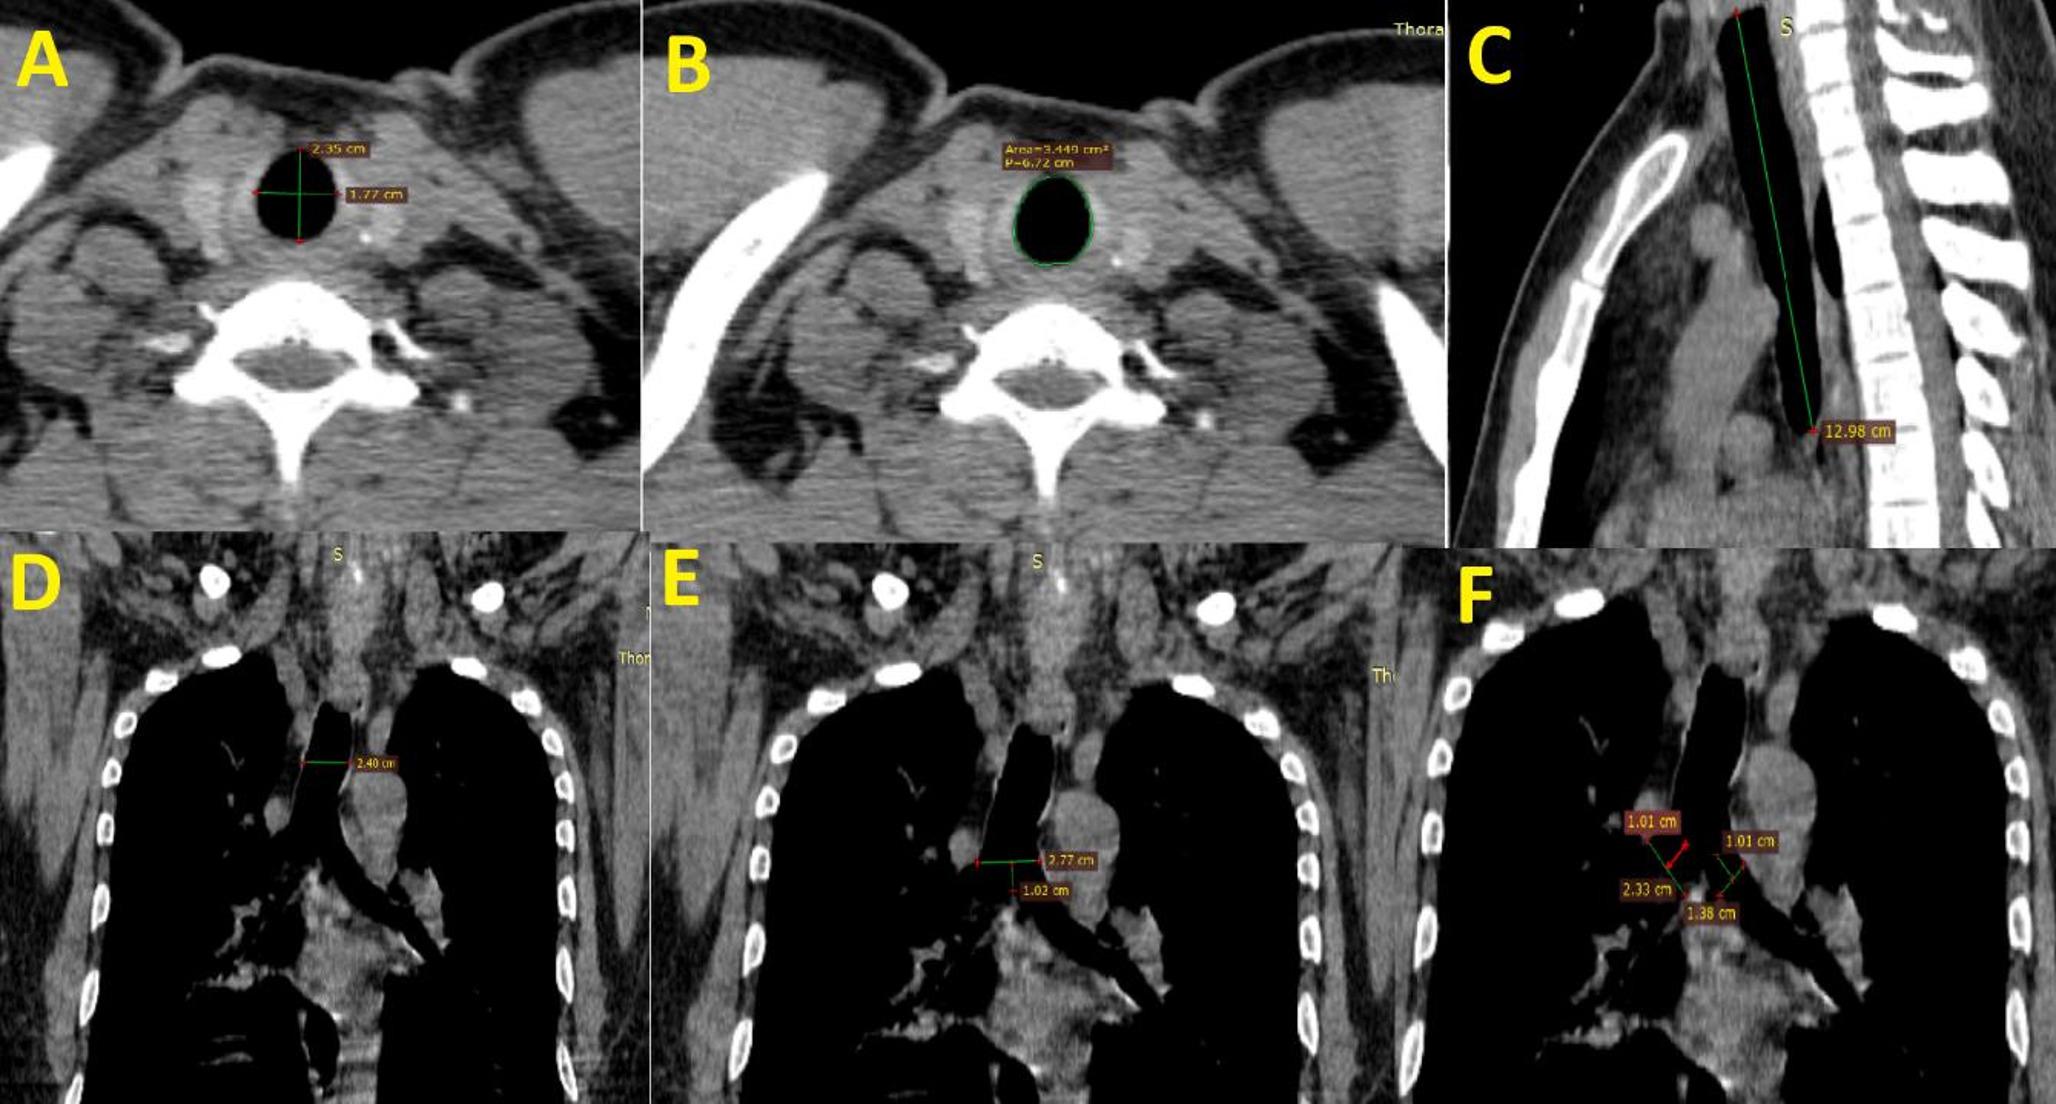

Tracheal morphometry using computed tomography in North Indian adults without any respiratory illness and its correlation with spirometry indices

The data regarding the tracheal morphometry in India, especially in vivo setting in healthy adults, is scarce. The current...